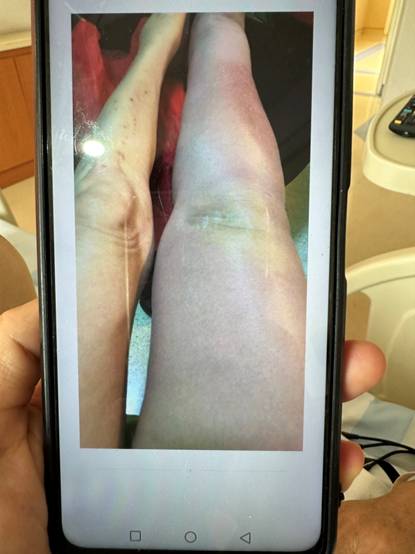

(梁阿姨拍下的右肢肿胀照片)

(梁阿姨术后照片)

术后第二天,梁阿姨原本肿胀的右腿已经明显消肿。术后一周,恢复良好,准备出院。喜悦之情,溢于言表,道不尽感激!